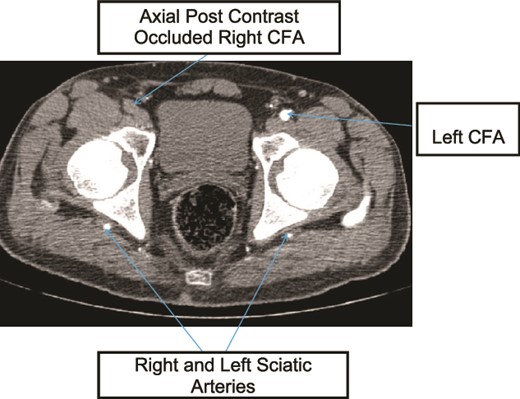

Case 1—axial image of LL CTA of the bilateral LL arteries at the level of the femoral head showing occlusion of the right CFA and bilateral PSA with larger caliber right PSA.